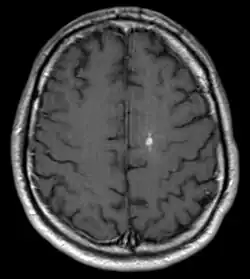

Developmental Venous Anomaly

Bei der Developmental Venous Anomaly (DVA) handelt es sich um eine gutartige, venöse Fehlbildung im Gehirn, die in den meisten Fällen symptomlos bleibt. Im typischen Fall zeichnet sich die Anomalie durch einen Strauß erweiterter, medullärer Venen aus, die auf eine kaliberstarke zentrale Drainagevene konvergieren. Die Venen sind an der normalen Drainage des Hirngewebes beteiligt, so dass ein Verschluss zu einer hämorrhagischen Infarzierung führen kann. Oft werden DVAs zufällig bei einer Magnetresonanztomographie des Gehirns entdeckt. Sie können jedoch auch mit anderen Gefäßfehlbildungen wie z. B. Kavernomen assoziiert sein.